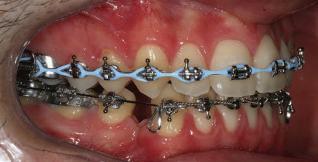

closed.

21Dental Tribune Bulgarian Edition / октомври 2022 г. ДИАГНОСТИЧНИ РЕЗУЛТАТИ: 1. Възраст на пациента: 21 години 2. Скелетен клас III (ANB 0) 3. Зъбен клас 3 4. Ръбцова захапка във фронта, кръстосана в дисталните участъци 5. Тясна горна челюст 6. Overjet – 0 мм, Overbite – 0 мм 7. Несъответствие на горната с долната средна линия 8. Единични контакти в ЦО 9. Хиподивергентен тип на растеж SN/MP – 33.5 10. Неравен гингивален контур 11. Неравна линия на усмивката 12. Тенденция за рецесии в долен фронт ПРЕПОРЪЧИТЕЛНО ЛЕЧЕНИЕ: Пълно ортодонтско лечение с метални брекети „Алекзандър“ Корекция на клас 3 захапката в областта на кучешките зъби с екстракция на първите пре молари в долна челюст Корекция на кръстосаната захапка в дистални участъци Коригиране на ръбцовата захапка във фронта Подобряване на ОJ и OB на пациента Стрипинг в долен фронт Подреждане на зъбите в горната и долната челюст Професионално хигиенизиране и профилактични дентални прегледи са препоръчителни на всеки 6 месеца. 1-ви месец След 1 месец са залепени брекети в горната челюст – поставена е еластична дъга. 016 NiTi. В долната челюст са елиминирани ротациите, поставена е стоманена дъга. 016SS, закалена с ток, и еластична верижка за затваряне на пространствата. 3-ти месец В долната челюст е поставена трета дъга – 17 x 25 NiTi с къси лигатури и верижка

В горната челюст се затварят пространствата с дъга .016SS и верижка. 5-и месец На 5-ия месец след залепяне на брекетите в долната челюст е поставена стоманена дъга 16 x 22 SS с четвъртито сечение, омега луп и тай бек. В горната челюст е поставена дъга 17 x 25 NiTi. Поради липсата на стабилни оклузални контакти са поставени лингвални верижки в областта на моларите, за да се предотврати нежелана ротация на 7-ите зъби. 6-и месец На 6-ия месец от началото на лечението са екстрахирани долните първи премолари, поставена е дъга 16 x 22 SS със затваряща чупка teardrop. Чупката се активира всеки месец по 1 мм с чинч-бек. клиничен случай | ортодонтия СТЪПКИ НА ЛЕЧЕНИЕТО Начало на лечението Лечението започва с поставяне на апарат за бърза експанзия в горната челюст. През първия месец от лечението са направени 24 оборота на апарата за експанзия. Залепени са брекети в долната челюст, поставена е дъга 17x25 CuNiTi, като са предпи сани клас 3 ластици (1/4”,4 1/2 oz) по време на сън, за да се осигури контрол върху торка на долните резци. Фиг. 2а Фиг. 3a Фиг. 4a Фиг. 3b Фиг. 4b Фиг. 3c Фиг. 4c Фиг. 3d Фиг. 4d Фиг. 3e Фиг. 4e Фиг. 5a Фиг. 5b Фиг. 5c Фиг. 5d Фиг. 5e Фиг. 6a Фиг. 6b Фиг. 6c Фиг. 6d Фиг. 6e Фиг. 7a Фиг. 7b Фиг. 7c Фиг. 7d Фиг. 7e Фиг. 2b Фиг. 2c Фиг. 2d